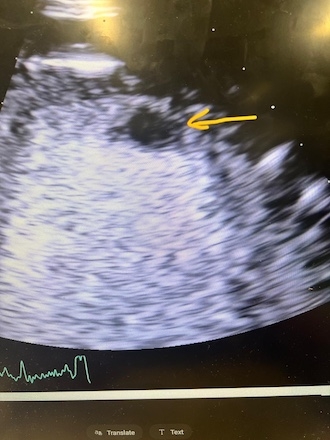

Case: A 56-year-old male with type 2 diabetes, presented with altered mental status, speech difficulty, and slurred speech. Vital signs were stable on admission. Labs showed hyperglycemia and elevated high-sensitivity troponin (peak: 3359 ng/L). EKG revealed sinus tachycardia at 109 bpm, T wave inversions in Leads 3, avF and inferior Q waves. Imaging consistent with an acute infarction in the posterior left MCA territory without hemorrhage. Transthoracic echocardiography demonstrated severely reduced ejection fraction (25–30%) with regional wall motion abnormalities and a well-defined apical thrombus.